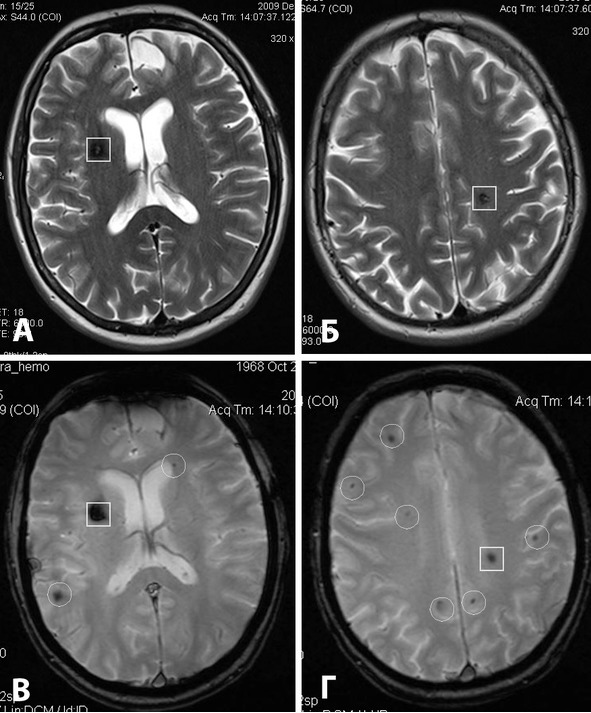

Среди режимов МРТ, которые могут оказать помощь в постановке диагноза, следует отметить МРТ-SWI, функциональную МРТ и диффузионно-тензорную МРТ. МРТ-SWI (T2* [GRE], SWAN и т.д.) основано на выявлении локальных неоднородностей магнитного поля (рисунок 18). Метод позволяет визуализировать даже небольшие очаги кровоизлияний и каверномы IV типа, часто не выявляющиеся при рутинных Т1 и Т2 режимах. Исследование выполнено в 16 случаях. Дополнительно визуализировать каверномы IV типа удалось у 4 человек. Метод дает ценную информацию для диагностики и прогноза, за счет большей чувствительности в выявлении множественных каверном.

Рис. 18. Диагностика каверном при МРТ в различных режимах. А, Б – МРТ в режиме Т2: кавернома глубинных отделов лобной доли справа; кавернома заднелобной области слева. В, Г – МРТ в режиме Т2* (GRE): дополнительно видны многочисленные (8) точечные патологические сосудистые образования (каверномы IV типа или телеангиоэктазии).